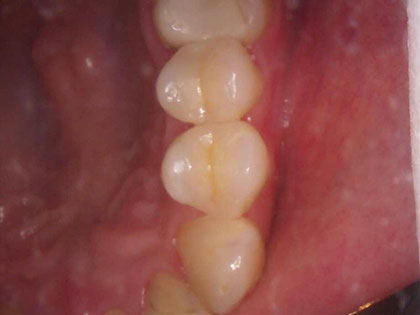

左下奥歯6、7番目にインプラント治療を行った症例

左下が腫れたり、噛むと痛いとの事で来院され、インプラント治療を希望された患者様の症例になります